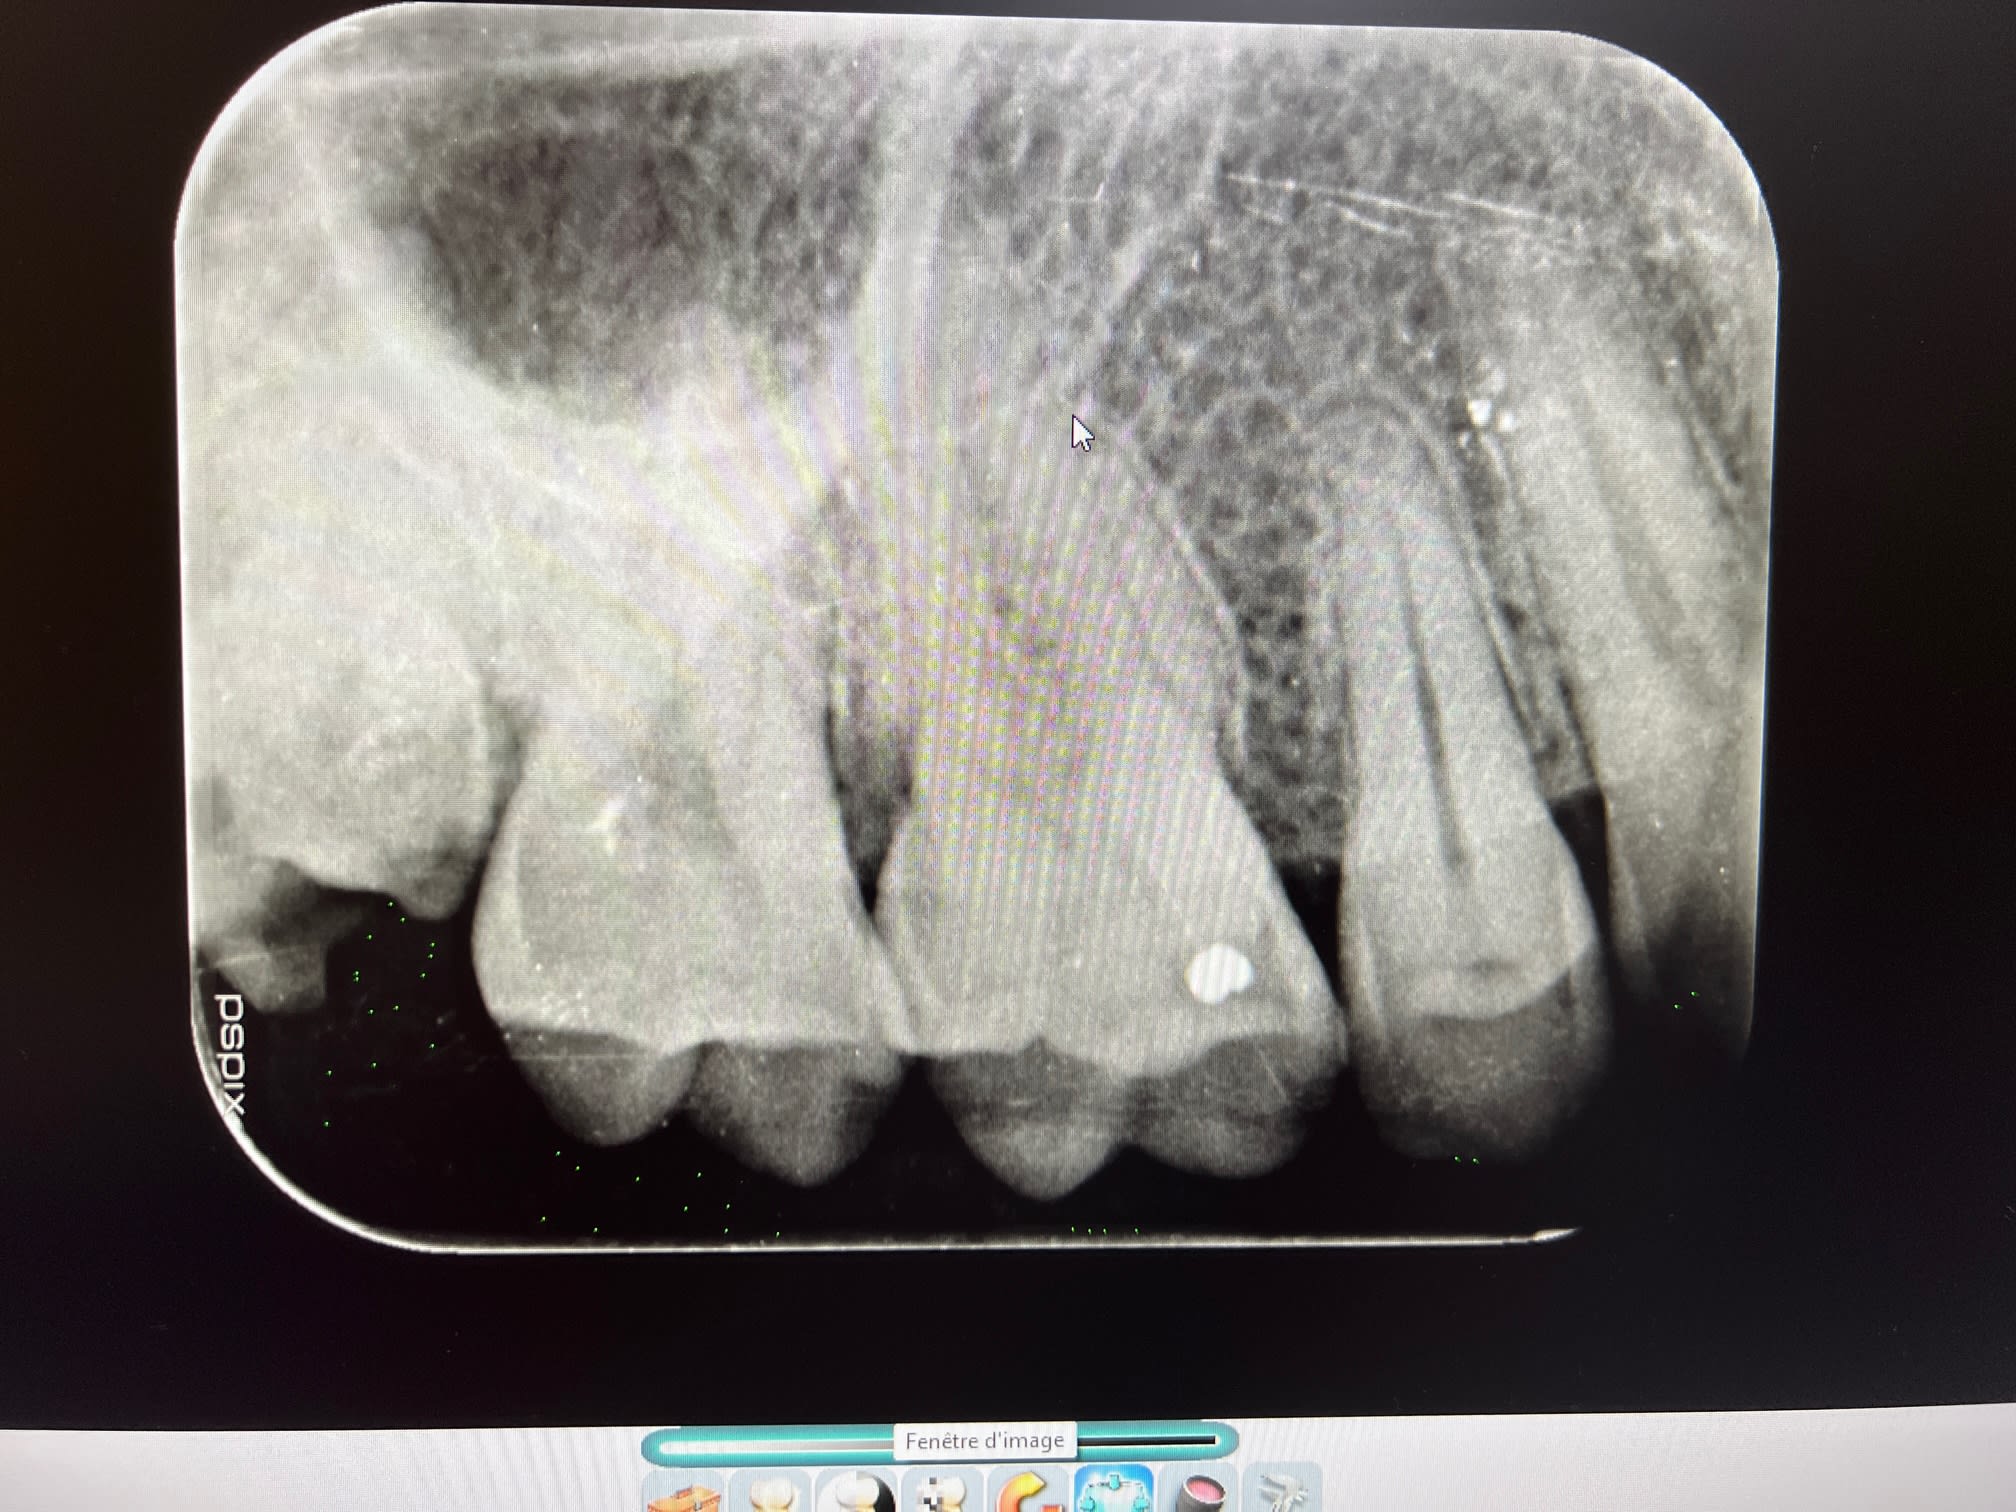

Patient adulte la 40aine, qui vient en urgence, pulpite sur la 8 maxillaire, très carie

Le problème va être la difficulté de l'extraction:

- dent carié en mésial donc pas un bon bon d'appui pour faire un effet de levier avec l'élévateur

- la dent est un peu en désinclusion, donc visible mais sous le plan d'occlusion donc pas facile d'accès, car la 7 la cache pas mal

- un os très dur (patient bruxo) donc sensation de lutter contre une dent ankylosé et donc rend la luxation difficile

- la dent a potentiellement aussi un apex courbé

la 18

La dent a été extraite, chiante comme prévu

Positionné légèrement en palatin, faible ouverture buccal, racine divergente, pas de point d'appui en mesial pour faire levier à cause de la carie, os dur (patient bruxeur)

J'ai du la couper de mesio a distal et sortir les 2 fragments qui son venu plutôt simplement ensuite